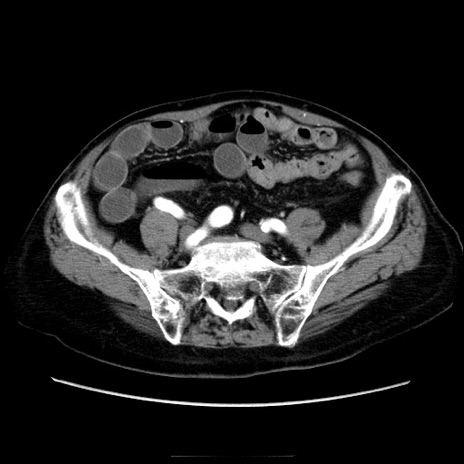

症例21(横断像)

【症例】70歳代男性

【主訴】腹痛

【現病歴】肝硬変・肝細胞癌にてかかりつけの方。約9時間前に食後より腹痛出現。症状が徐々に増悪し、嘔吐出現したため来院。

【既往歴】肝硬変、肝細胞癌(RFA、TACE後)

【身体所見】意識清明、表情苦悶様、BT 36℃、BP 129/78mmHg、P 88bpm、SpO2 97%(RA)、右上腹部から心窩部にかけて圧痛あり、反跳痛なし、筋性防御あり。

【データ】WBC 5800、CRP 0.16